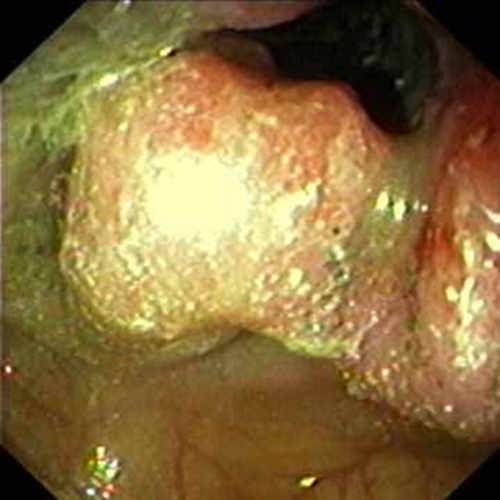

右半結腸癌圓形未分化癌常見 臨床 特點